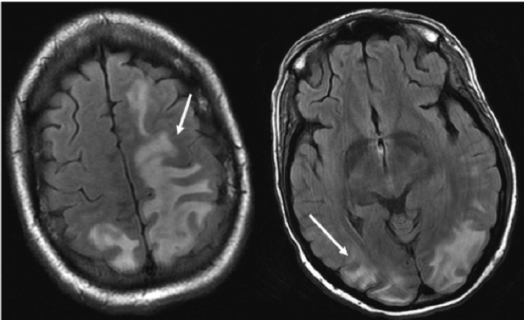

Magnetic resonance imaging (MRI) is more sensitive and has a better correlation with underlying pathophysiology compared with CT.13 In addition, MRI can differentiate PRES from other conditions that can mimic PRES. T2-weighted and T2 fluid-attenuated inversion recovery (FLAIR) images can detect vasogenic edema related to PRES. Figure 4 and Figure 5 show MRI images of PRES.

Figure 5. Coronal T2-Fluid-Attenuated Inversion Recovery Magnetic Resonance Images Showing Involvement of Parietal Lobes and Occipital Characteristic of Posterior Reversible Encephalopathy Syndrome12